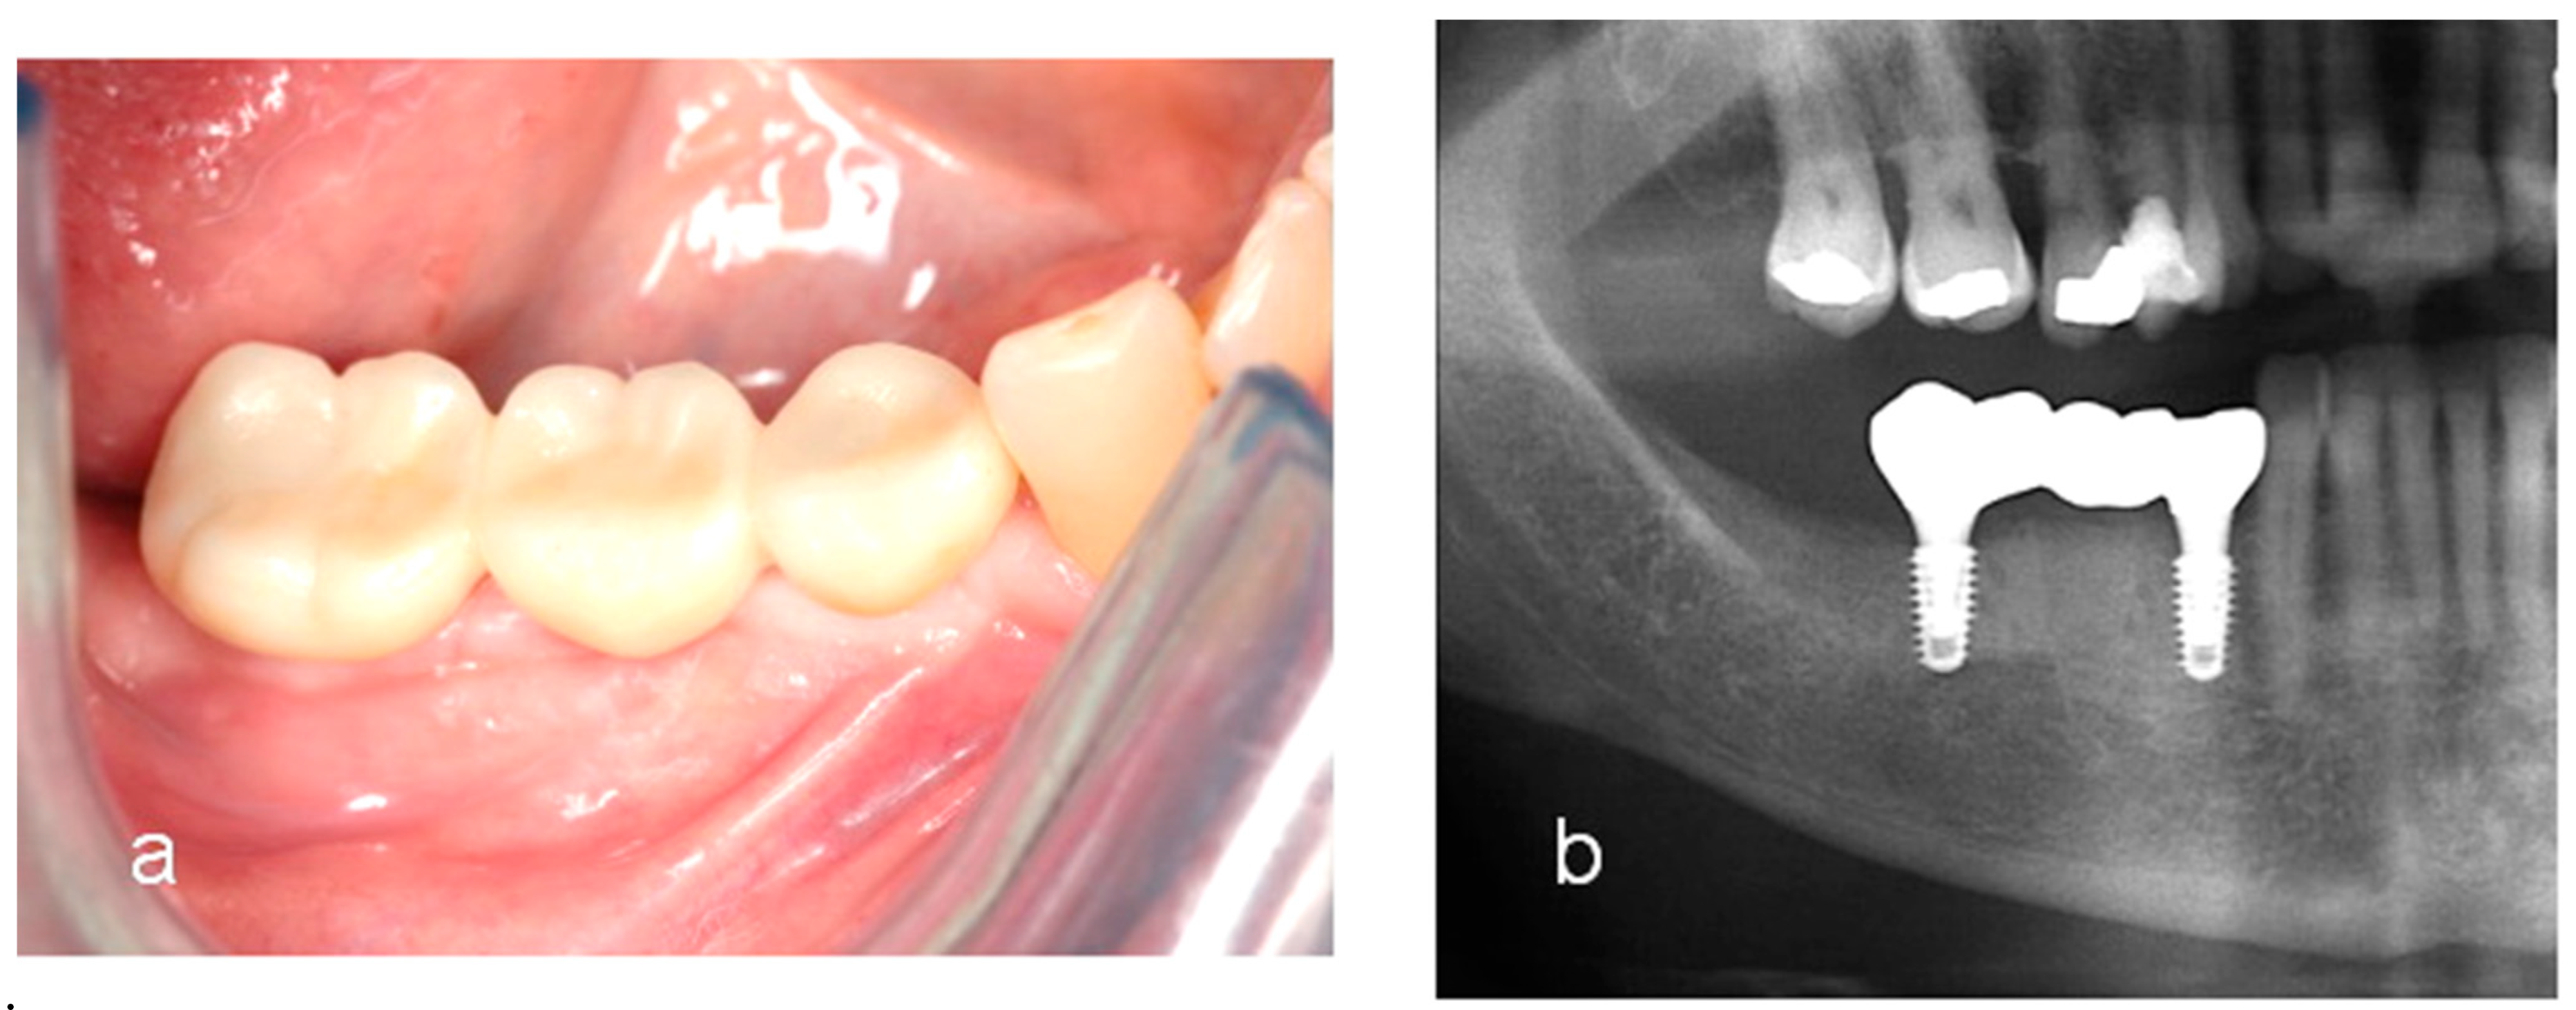

- Woo, R.H.; Kim, H.G.; Kim, G.; Park, W.E.; Sohn, D.S. Simplified 3-dimensional ridge augmentation using a tenting abutment. Adv. Dent. Oral. Health 2020, 12, 185–205. [Google Scholar]

- Sohn, D.S. Reconstruction of three-dimensional alveolar ridge defects utilizing screws and implant abutments for the tent-pole grafting’ techniques. In Essential Techniques of Alveolar Bone Augmentation in Implant Dentistry, 2nd ed.; Tolstunov, L., Ed.; Wiley Blackwell: Hoboken, NJ, USA, 2023; pp. 404–418. [Google Scholar]